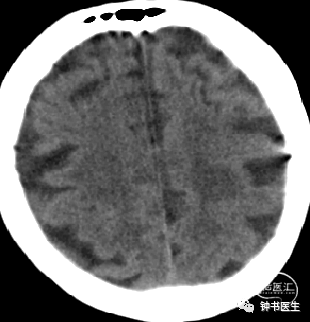

2017-7-6 CT

2017-7-7 CT

2017-7-12 CT